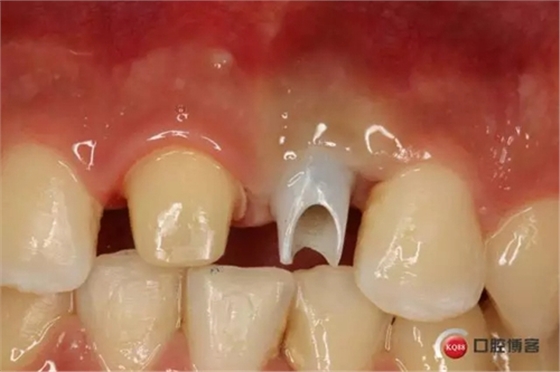

藻酸鹽對(duì)頜取模,超硬石膏灌注。發(fā)加工廠,與技工溝通注意事項(xiàng),等修復(fù)體做好后,檢查模型。是否就位,是否密合,預(yù)約患者復(fù)診戴牙,消毒修復(fù)區(qū),旋出愈合基臺(tái),定位器指導(dǎo)安放修復(fù)基臺(tái),試戴冠,調(diào)磨鄰接及 咬合至合適,拋光,患者滿意,加力扳手加力至30N,拍X片見(jiàn)就位良好,特芙蓉及暫封膏封中央螺絲孔,聚羧酸鋅粘固劑粘固,或是樹(shù)脂水門汀粘固,清理多余粘結(jié)劑,光固化樹(shù)脂封螺絲孔,拋光。術(shù)后注意隨訪。